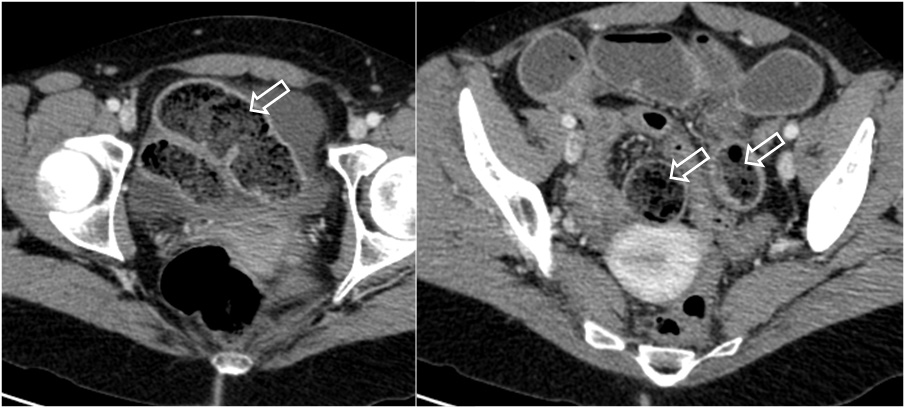

SIGNO DE LAS HECES EN INTESTINO DELGADO

En la TC abdominal, la presencia de burbujas de gas dentro del intestino delgado (patrón «en miga de pan») es siempre anormal, y con frecuencia se debe al enlentecimiento del tránsito intestinal, digestión incompleta del contenido digestivo, sobrecrecimiento bacteriano y aumento de la absorción de agua. Estas alteraciones suelen deberse a obstrucción de intestino delgado aunque también se ha descrito en otras anomalías severas de delgado como enfermedad infecciosa o metabólica. La combinación de este signo y dilatación de asas de delgado es altamente sugestiva de obstrucción , especialmente cuando existe colapso del intestino distal.

En las imágenes vemos este signo (flechas blancas) en una paciente con fibrosis quística y síndrome de obstrucción de intestino distal.